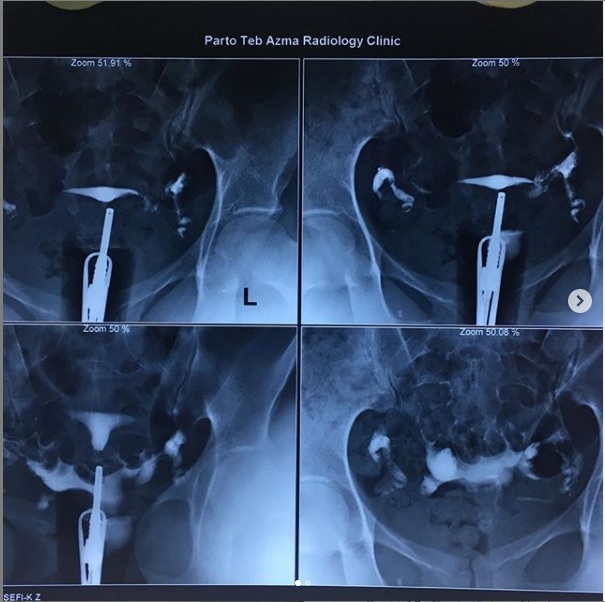

بیمار در وضعیت زنان (به پشت خوابیده، زانوهای خم شده و از هم باز)، زیر دستگاه اشعه ایکس قرار می گیرد. پزشک یک اسپکولوم را وارد واژن میکند، سپس یک کانولا را در دهانه رحم قرار میدهد که از طریق آن یک ماده حاجب تزریق میکند. این به داخل رحم و لوله های فالوپ گسترش می یابد. اشعه ایکس برای مشاهده پیشرفت خوب محصول و تجسم اندام ها گرفته می شود.

هیستروسالپنگوگرافی توسط رادیولوژیست انجام می شود. معاینه بدون بیهوشی انجام می شود. بیمار در موقعیت "زنان و زایمان" مستقر می شود. پزشک اسپکولوم را قرار می دهد، دهانه رحم را ضد عفونی می کند و سپس یک پروب را با روش طبیعی وارد رحم می کند. او به تدریج ماده حاجب را تزریق می کند. به طور معمول، ماده حاجب به تدریج رحم و لوله های فالوپ را کدر می کند تا زمانی که به حفره صفاقی منتقل شود.

چندین عکس رنگی رحم قبل، حین و بعد از تزریق محصول گرفته می شود و این در موقعیت های مختلف:

اشعه ایکس بدون آماده سازی (جستجو برای کلسیفیکاسیون لگن)؛

اشعه ایکس پر شدن ضعیف (پولیپ ها یا فیبروم های زیر مخاطی را برجسته می کند).

اشعه ایکس پر شدن لوله (ارزیابی وضعیت مخاط لوله).

عکس پروفایل (ارزیابی موقعیت رحم و مسیر لوله های فالوپ)؛

اشعه ایکس دیررس (بررسی گردش خون صفاقی، جستجو برای چسبندگی لگن).

در اصل، HSG یک ارزیابی رادیوگرافی از حفره رحم و لوله های فالوپ با استفاده از فلوروسکوپی سرپایی بلادرنگ با تزریق ماده حاجب رادیویی مات از طریق کانال دهانه رحم را نشان می دهد. کانال دهانه رحم، کانتور حفره رحم و لومینای رحم و لوله شامل بخش های قرنیه، ایستمی و آمپولری و تعیین